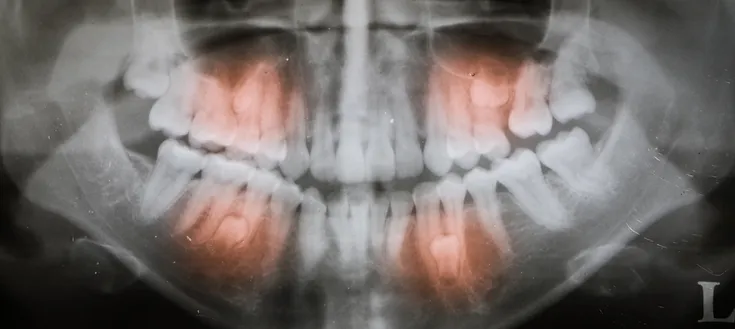

Exposure of impacted teeth is a surgical procedure aimed at revealing impacted teeth that are trapped within the jawbone without a pathway to erupt into the oral cavity. This procedure allows an orthodontic specialist to connect to these impacted teeth and guide them to their proper position.